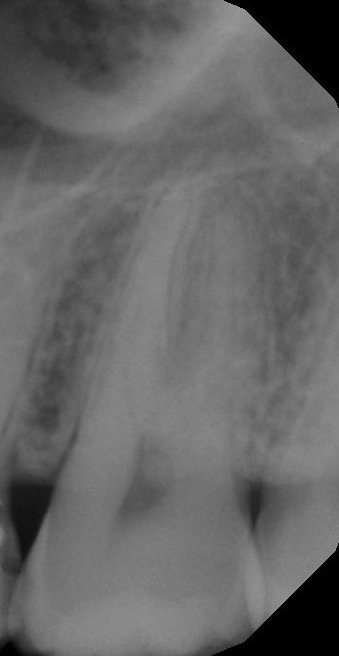

Чтобы говорить о вине врача, необходимо видеть снимки до лечения. Думаю, что проблема в другом. Выложите сюда рентген-снимок, я Вам все расскажу.

Спасибо за ответ! Вот снимок зуба, который беспокоил до пломбирования.

• На первичном снимке никакой трещины и патологии я не вижу. Сложно сейчас говорить, что произошло, но по этому снимку я бы не трогал зуб вовсе. Рекомендую для начала сменить доктора и обратиться к более грамотному специалисту.